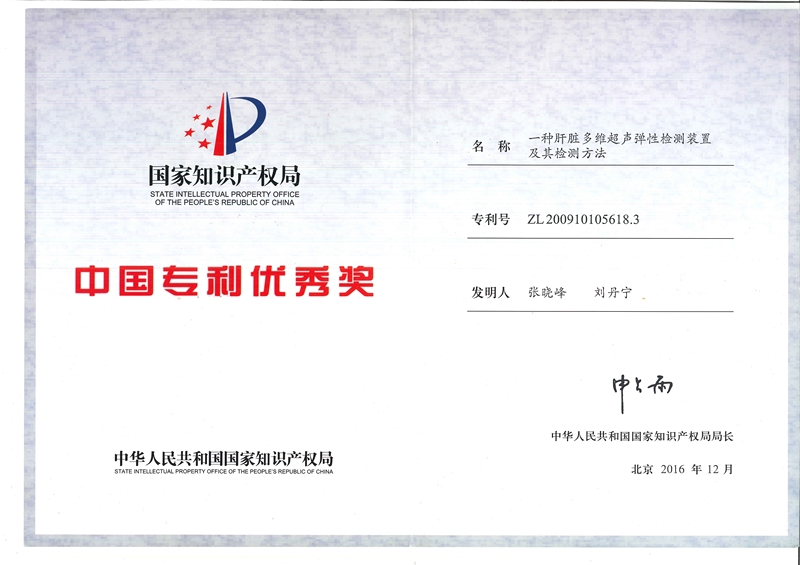

дё“еҲ©дјҳејӮеҘ–-17еұҠ

дё“еҲ©дјҳејӮеҘ–-18еұҠ